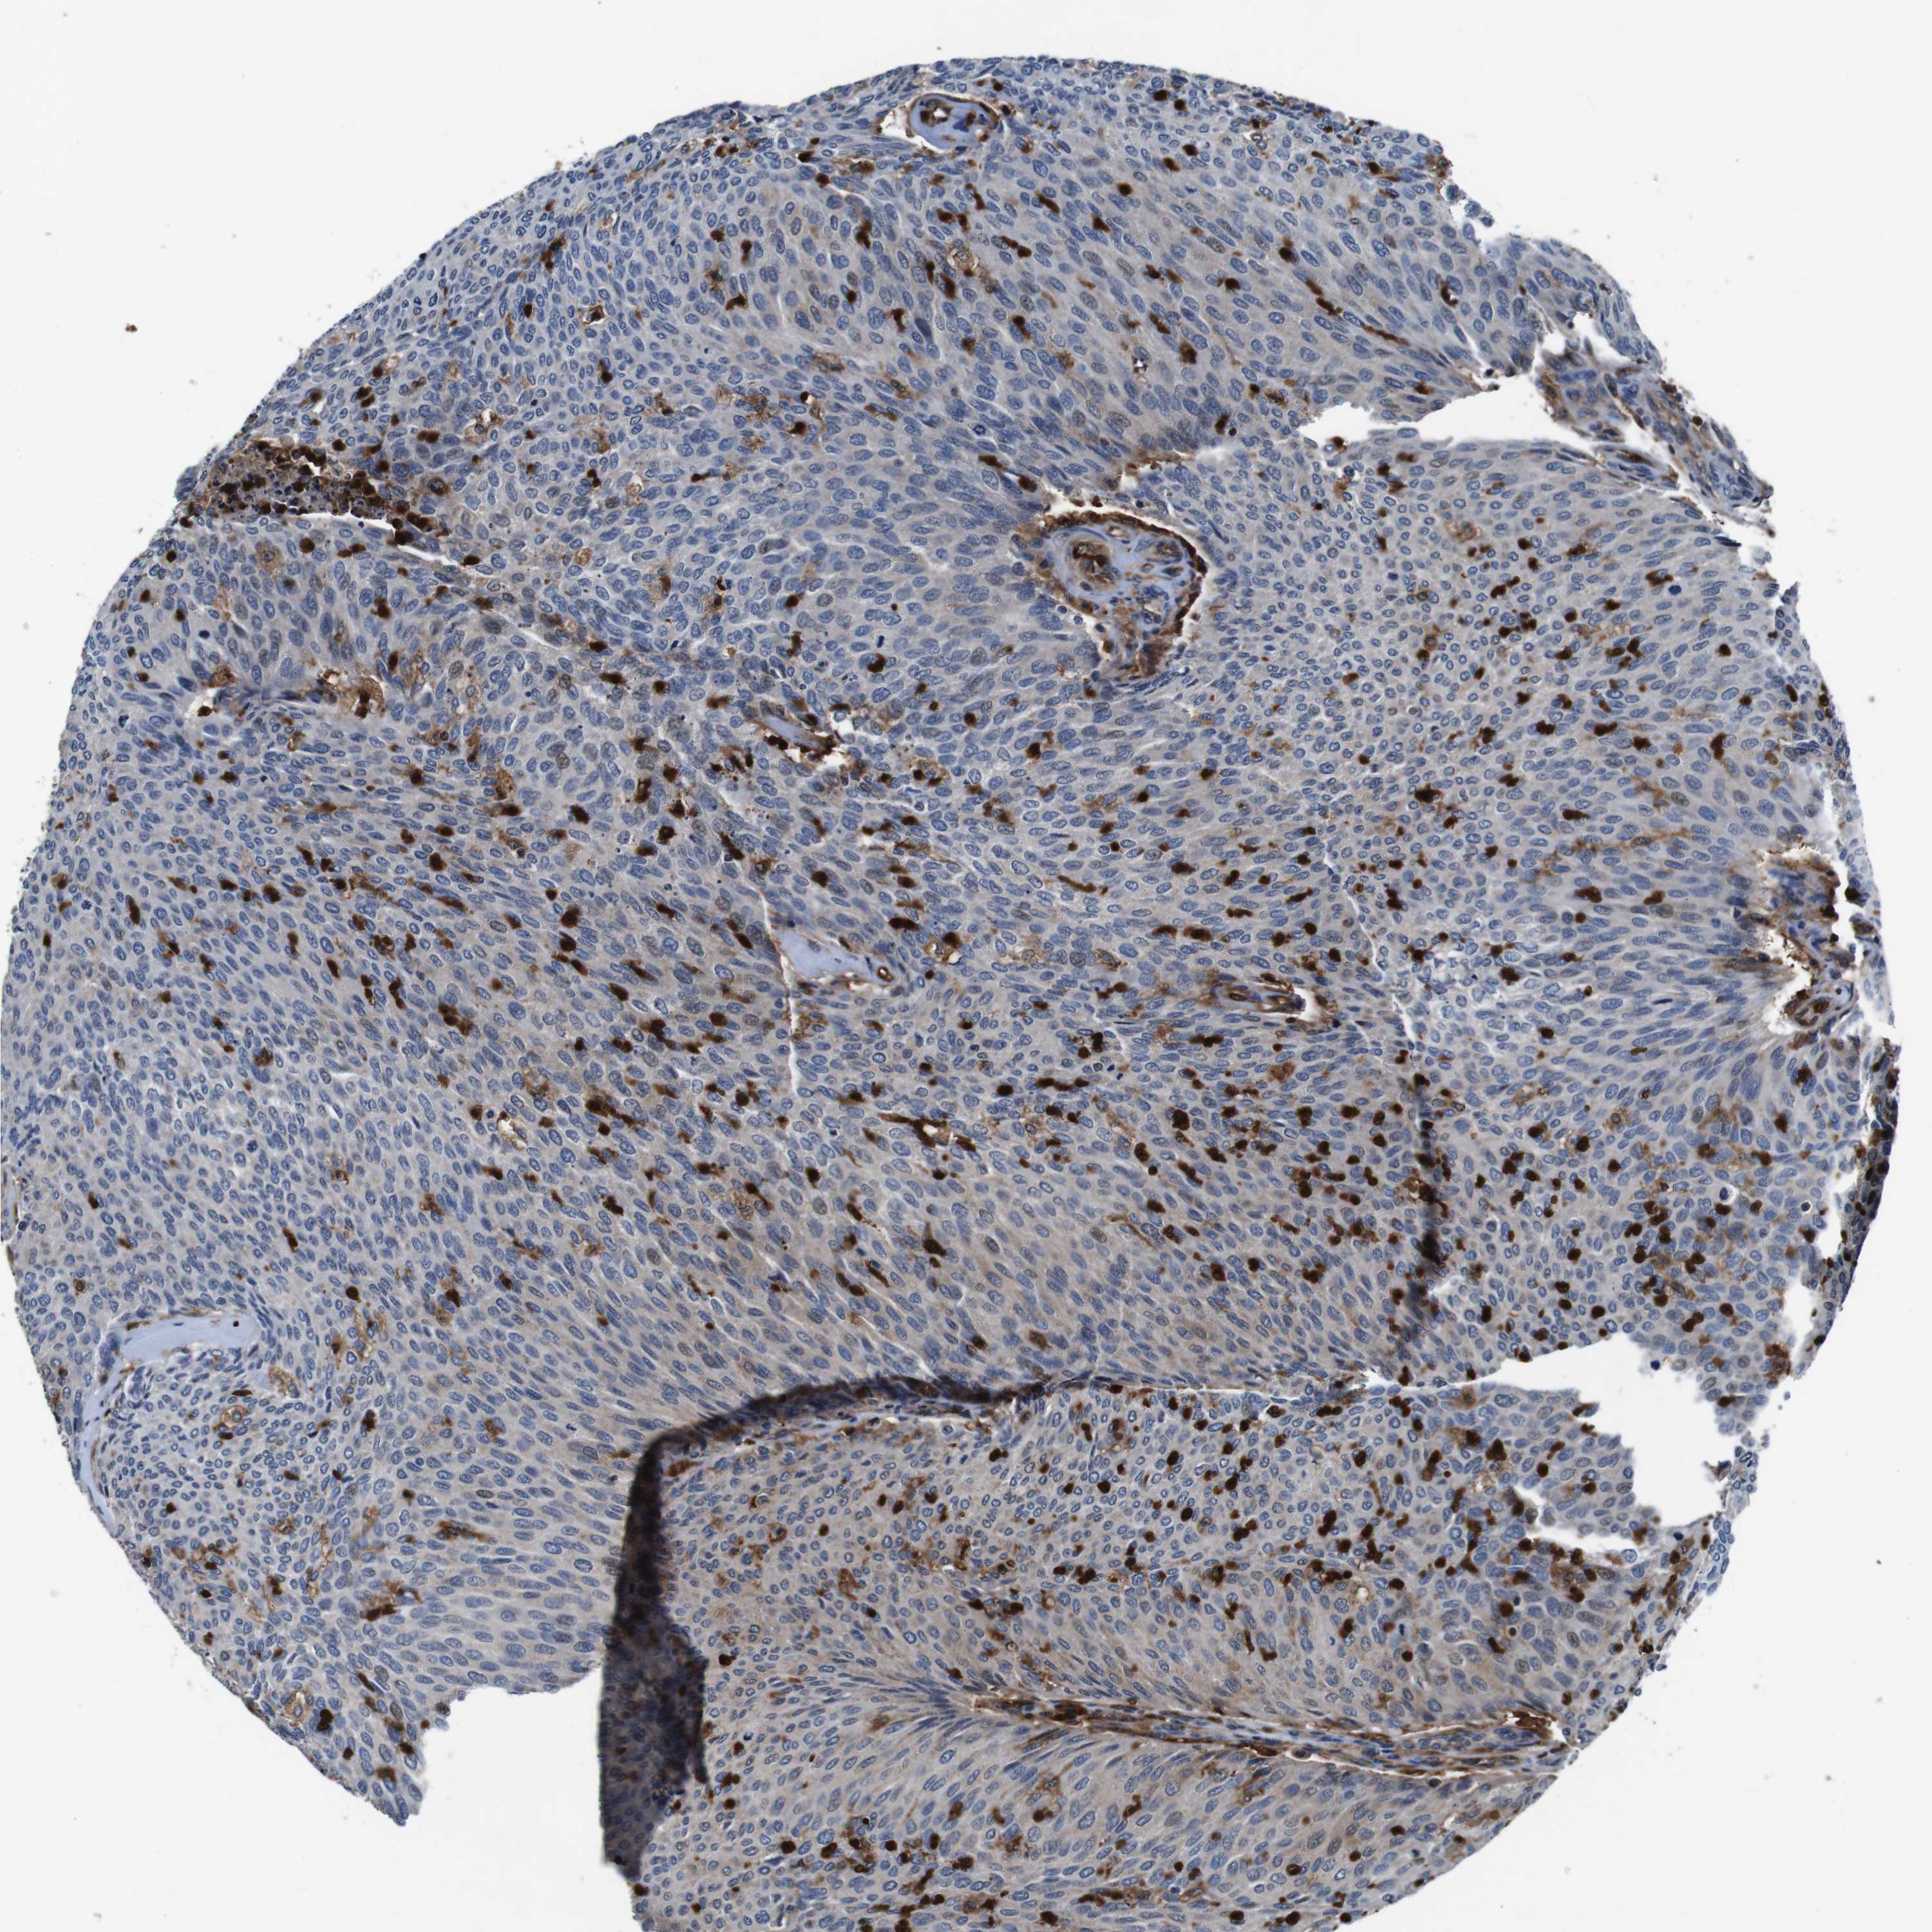

UROTHELIAL CANCER - Protein expressioni

A mouse-over function shows sample information and annotation data. Click on an image to view it in a full screen mode. Samples can be filtered based on level of antibody staining by selecting one or several of the following categories: high, medium, low and not detected. The assay and annotation is described here.

Note that samples used for immunohistochemistry by the Human Protein Atlas do not correspond to samples in the TCGA dataset.

Antibody stainingi

Antibody staining in the annotated cell types in the current human tissue is reported as not detected, low, medium, or high, based on conventional immunohistochemistry profiling in selected tissues. This score is based on the combination of the staining intensity and fraction of stained cells.

Each image is clickable and will lead to virtual microscopy that enables deeper exploration of all samples and also displays staining intensity scores, fraction scores and subcellular localization as well as patient and tissue information for each sample.

HPA011271

HPA011272

CAB013023

CAB035987

CAB058693

CAB080415

Staining

High

Medium

Low

Not detected

Intensity

Strong

Moderate

Weak

Negative

Quantity

>75%

75%-25%

<25%

None

Location

Nuclear

Cytoplasmic/membranous

Cytoplasmic/membranous,nuclear

Urothelial carcinoma, Low grade

Urothelial carcinoma, High grade

Urothelial carcinoma, NOS